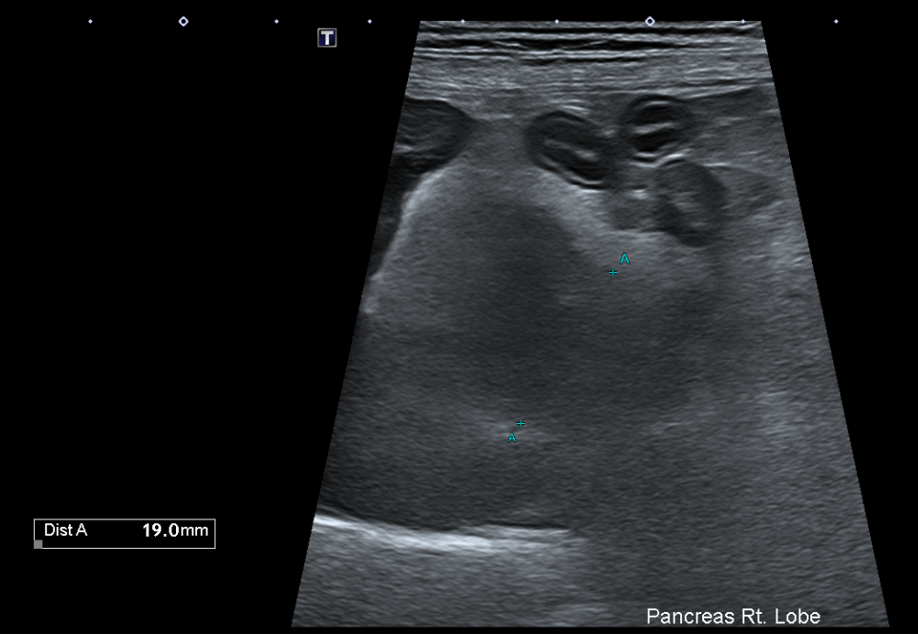

복부초음파

또한 복부 초음파상에서 뚜렷한 췌장 비후, 저에코성 음영, 주변 복막의 고에코성 소견 -> 확인되어 췌장염이 강력 의심되는 상황이었습니다.

Figure 2. 췌장 비후와 주변 복수 확인됨.

환자의 경우 뚜렷한 소화기 증상, 뚜렷한 염증 소견과 QPL 수치 상승, 복부초음파상 췌장염 비후, 복수 소견 확인되어 췌장염으로 진단되었습니다.

복부 초음파 검사

복부 초음파 검사는 췌장염 진단에 매우 유용한 검사입니다.- 췌장의 비대

- 췌장 주변 지방의 에코 변화

- 췌장 주변 Fluid 축적